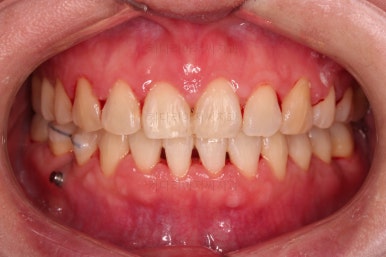

1. 초진

초진 시 입안의 모습입니다.

당장 눈에 띄는 부분은 아래 앞니 사이에 틈새가 있어 치석도 많이 쌓여있는 상황이고요.

윗니-아랫니를 각각 보면 치아가 썩고 부러져 뿌리만 남은 치아가 많이 보입니다.

남은 치아들도 곳곳에 충치가 보이고요.

또 전반적으로 앞니가 앞으로 밀려나와 뻐드러져 있는 모습도 관찰되네요.